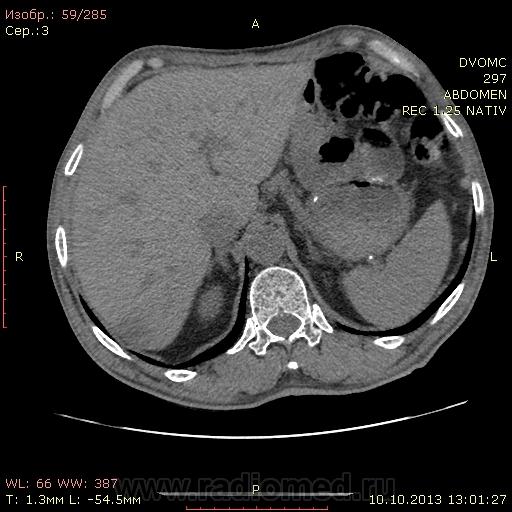

69 лет. КТ контроль от августа. Посте очередного курса химии. Начало истории здесь http://www.radiomed.ru/cases/kt-bryushnoi-polosti-adenokartsinoma-zheludka-sostoyanie-posle-rezektsii-zheludka-mts-v-pechen

Сегодня выглядит так. DICOM здесь http://files.mail.ru/2A18DCE6A6AA4546B51713D2F9C9E91A

На мой взгляд метастазов новых нет, но старые увеличились и один из пораженных л\у также увеличился.

Расценивать как "отрицательная"?

"но старые увеличились и один из пораженных л\у также увеличился.

Расценивать как "отрицательная"?"

А как ещё?